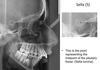

When would you consider taking a lateral ceph?

For patients with skeletal discrepancies (i.e class II or III antero-posterior)

What information can you gather from a cephalometric x-ray?

Antero-posterior and vertical dimensions